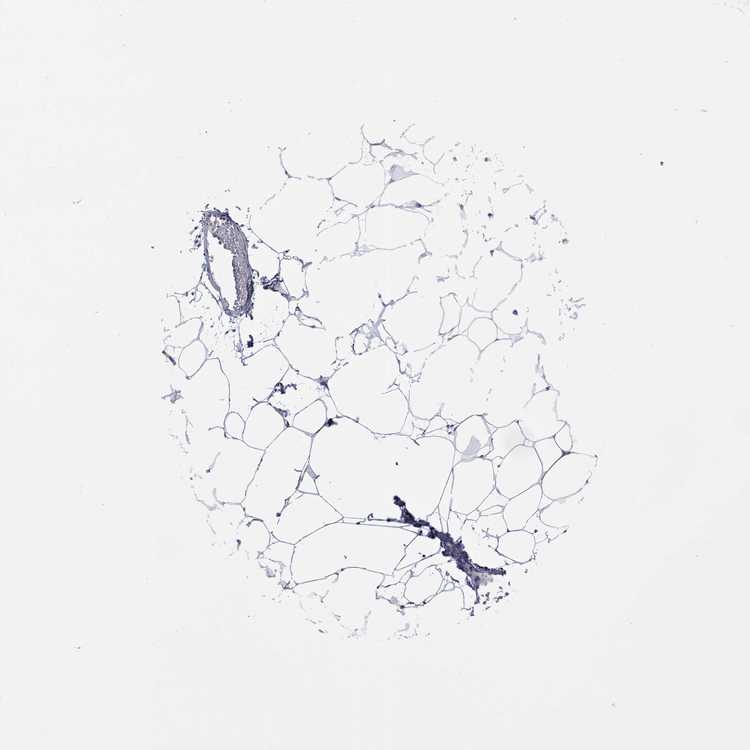

TISSUE PRIMARY DATA BREAST Show tissue menu

BREAST - Antibody stainingi

Antibody staining in the annotated cell types in the current human tissue is reported as not detected, low, medium, or high, based on conventional immunohistochemistry profiling in selected tissues. This score is based on the combination of the staining intensity and fraction of stained cells.

Each image is clickable and will lead to virtual microscopy that enables deeper exploration of all samples and also displays staining intensity scores, fraction scores and subcellular localization as well as patient and tissue information for each sample.

Antibody HPA035516Antibody HPA035517Antibody HPA061469

Adipocytes Not detectedLowNot detected

Glandular cells LowMediumLow

Myoepithelial cells LowLowNot detected